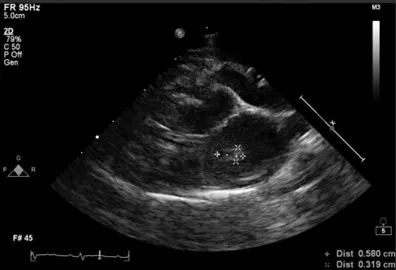

Diagnostics were triaged in order of importance because of the severity of disease and suspicion of a previous thromboembolic event, as well as to reduce patient stress. An echocardiogram to evaluate for underlying cardiac disease was determined to be top priority; results revealed concentric hypertrophy of the left ventricle (5.55 mm), papillary muscle hypertrophy, endomyocardial fibrosis, and end-systolic cavity obliteration. The left atrium was moderately dilated (left atrium:aorta, 2.3; 2D left atrial diameter [LAD], 22 mm; M-mode LAD, 23 mm) with presence of spontaneous echo contrast (ie, smoke). A moderately sized thrombus was observed in the left atrial appendage (Figure 1).

FIGURE 1 Left atrial thrombus in a cat with a history of hypertrophic cardiomyopathy presented for lameness. A slightly obliqued, right parasternal, 4-chamber-long axis view of the heart reveals a thrombus in the left atrium, which is moderately dilated.